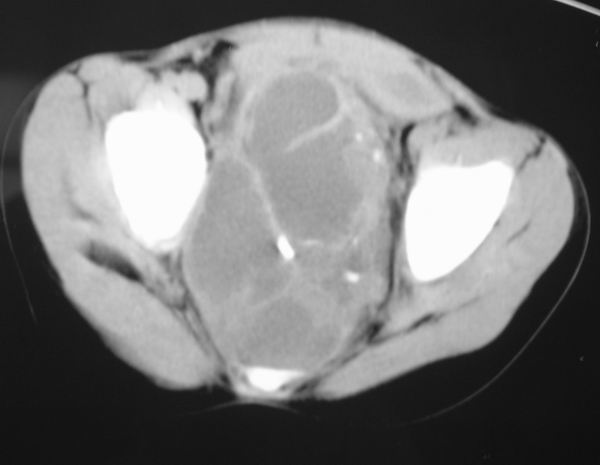

标题: PED0321:F 7 骶尾部肿瘤 有病理结果 [打印本页]

标题: PED0321:F 7 骶尾部肿瘤 有病理结果

骶尾部肿瘤 有病理结果

畸胎瘤

考虑畸胎瘤可能性大。骶尾骨无破坏。不考虑脊索瘤。

骶骨没有发现骨质破坏,畸胎瘤的可能性大